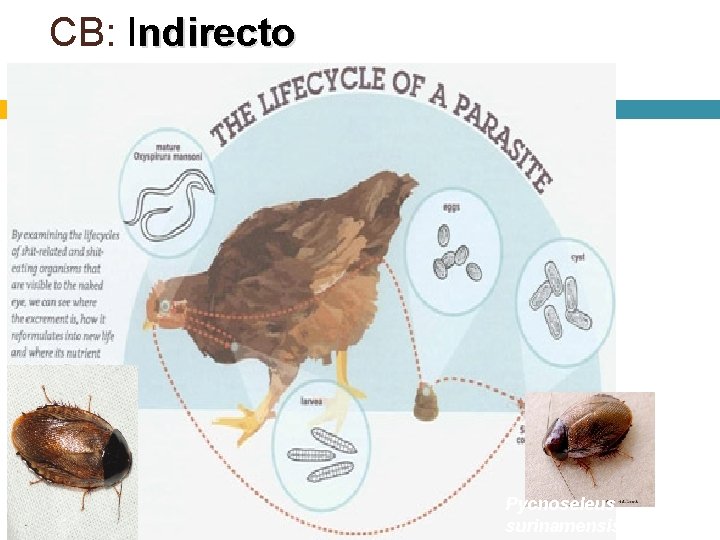

CB: Indirecto I Pycnoseleus surinamensis